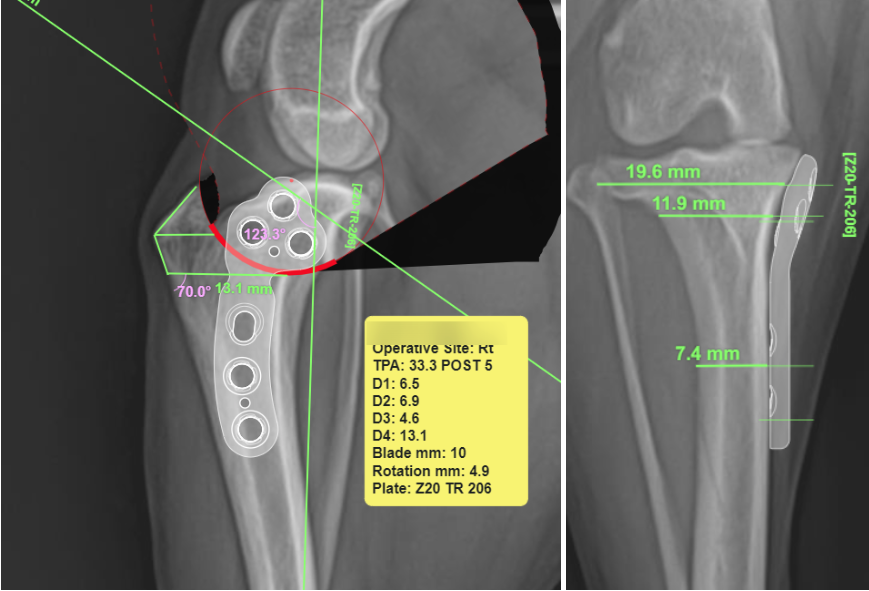

강아지 TPLO 수술 계획 (TPA 측정)

아이들마다 다리 구조와 경골 경사각이 모두 다르기 때문에 수술 전 계획이 정밀하게 이루어져야 수술이 잘 이루어질 수 있습니다. 양산 에스동물병원에서는 강아지 TPLO 수술 전 TPA VIEW를 이용하여 아이의 TPA를 정확히 측정하고 절골할 위치와 회전 각도, 사용할 플레이트 사이즈까지 확인 후 수술을 진행합니다.

양산 에스동물병원 강아지 TPLO 수술 계획 (TPA 측정) / 출처: 에스동물메디컬센터